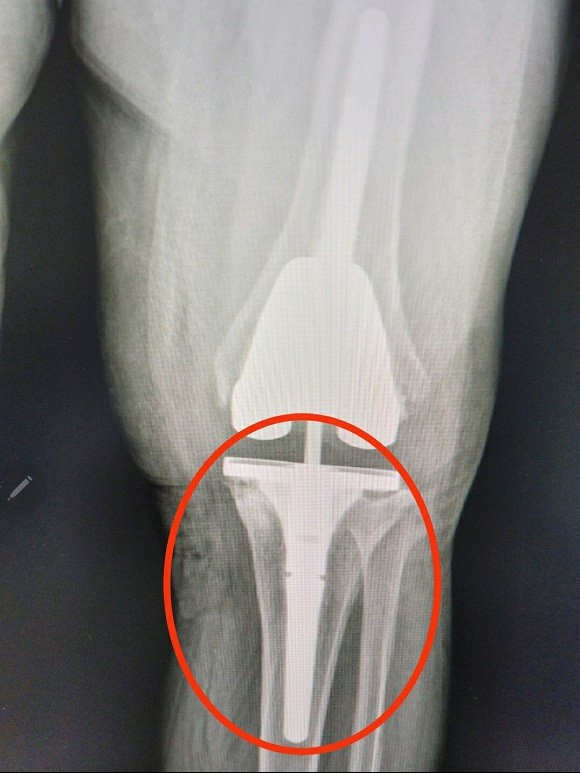

"재수술 불가능한 의료기구 납품" 포항 A병원 논란…"철저히 조사해야"